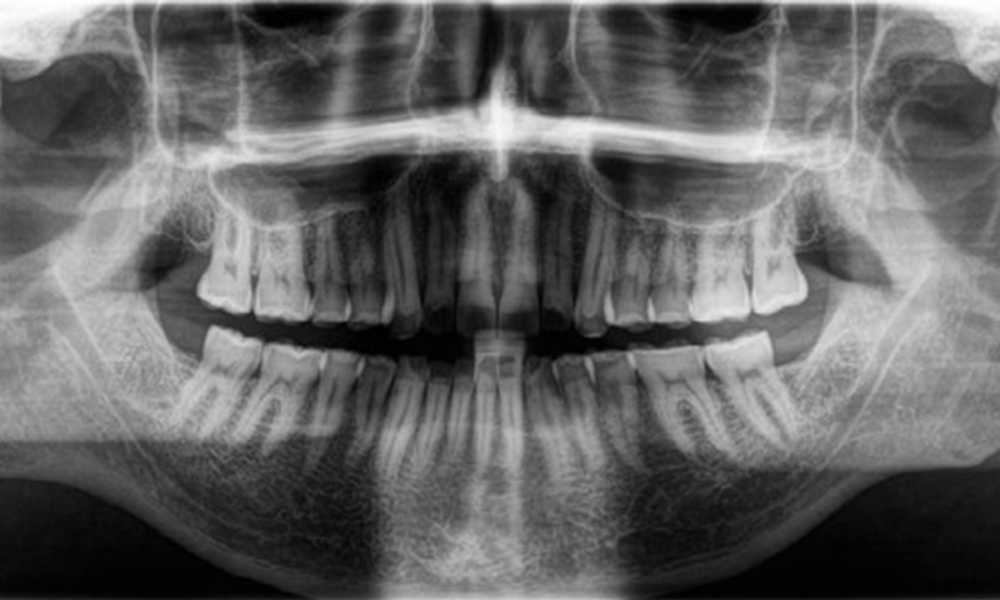

Radiologischer Befund

Es zeigt sich ein vollbezahntes, kariesfreies Erwachsenengebiss ohne radiologisch erkennbaren Knochenabbau (Abb. 6). Radiologischer Schmelz- und Höckerverlust sind insbesondere an 36 und 37 festzustellen.